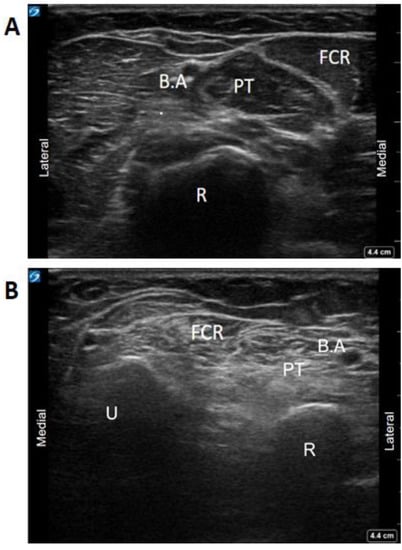

4.5. Visual Ergonomics Using Ultrasound